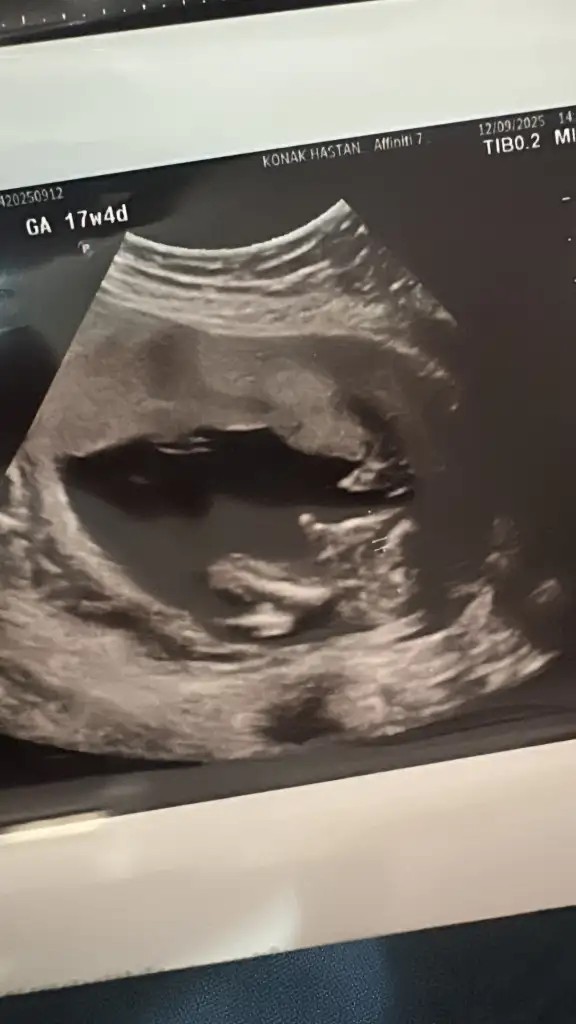

Maşallah canım darısı başıma fotosu var mı bir de doktor mu tahminde bulunmuştu nuba göre kız diyeBenimki tutmadi, 11 haftada kiz denildi 16. Haftada pipi gorduk

Detayli ultrasonda doktor 70% ihtimal demisti Nuba gore. Fotoyu chatgpt ye yukleyip sordugumda o da kiz demisti fakat erkek ciktii sonuc olarakMaşallah canım darısı başıma fotosu var mı bir de doktor mu tahminde bulunmuştu nuba göre kız diye

Benim de yapay zekalar kız diyor detaylıda mı belli oldu fotoğraf varsa atar mısınız çok merak ettim. Bir de özel hastane miydi ve doktorunuz tecrübeli miydiDetayli ultrasonda doktor 70% ihtimal demisti Nuba gore. Fotoyu chatgpt ye yukleyip sordugumda o da kiz demisti fakat erkek ciktii sonuc olarak1 aya kesinlesir sizin de

Çok teşekkür ediyorum canım ama nubu kız derim dedi bir hayli kişiye sordum onlar da kız dedi. Nuba göre senşn nasıldıBenim tutmadı doktorum kız demişti 13 te nipt testim çıktı erkek olduğunu öğrendik 14 te de gösterdi zaten oğluşumbiraz daha bekleyin derim sağlıkla gelsin bebeğiniz

Benimde nub kız görünüyordu canım erken dönemde zaten kız olarak görünüyor tüm bebekler eğer biraz daha değişmezse kızdır erkek erken gösteriyor geneldeÇok teşekkür ediyorum canım ama nubu kız derim dedi bir hayli kişiye sordum onlar da kız dedi. Nuba göre senşn nasıldı